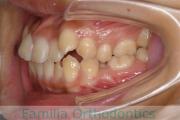

No.22V-449

- 主な症状:

- 上顎前突

- その他の症状:

- 叢生

- 年齢:

- 14歳

- 性別:

- 男性

- 抜歯部位

- 上:

- 44

- 下:

- 8448

- 主な使用装置:

- FEA

- 治療にかかった費用:

- 87万円

歯並びをきれいにしたいということで来院されました。上下左右から小臼歯を抜歯して、マルチブラケット法を行っています。2年弱、25回程度の通院が必要でした。

かなり強い叢生(でこぼこ、凹凸、ガタガタ)ですので、保定をしっかりしないと後戻りのリスクがあります。

- ≫治療前

-

上顎

下顎

前歯の関係など

右側

正面

左側